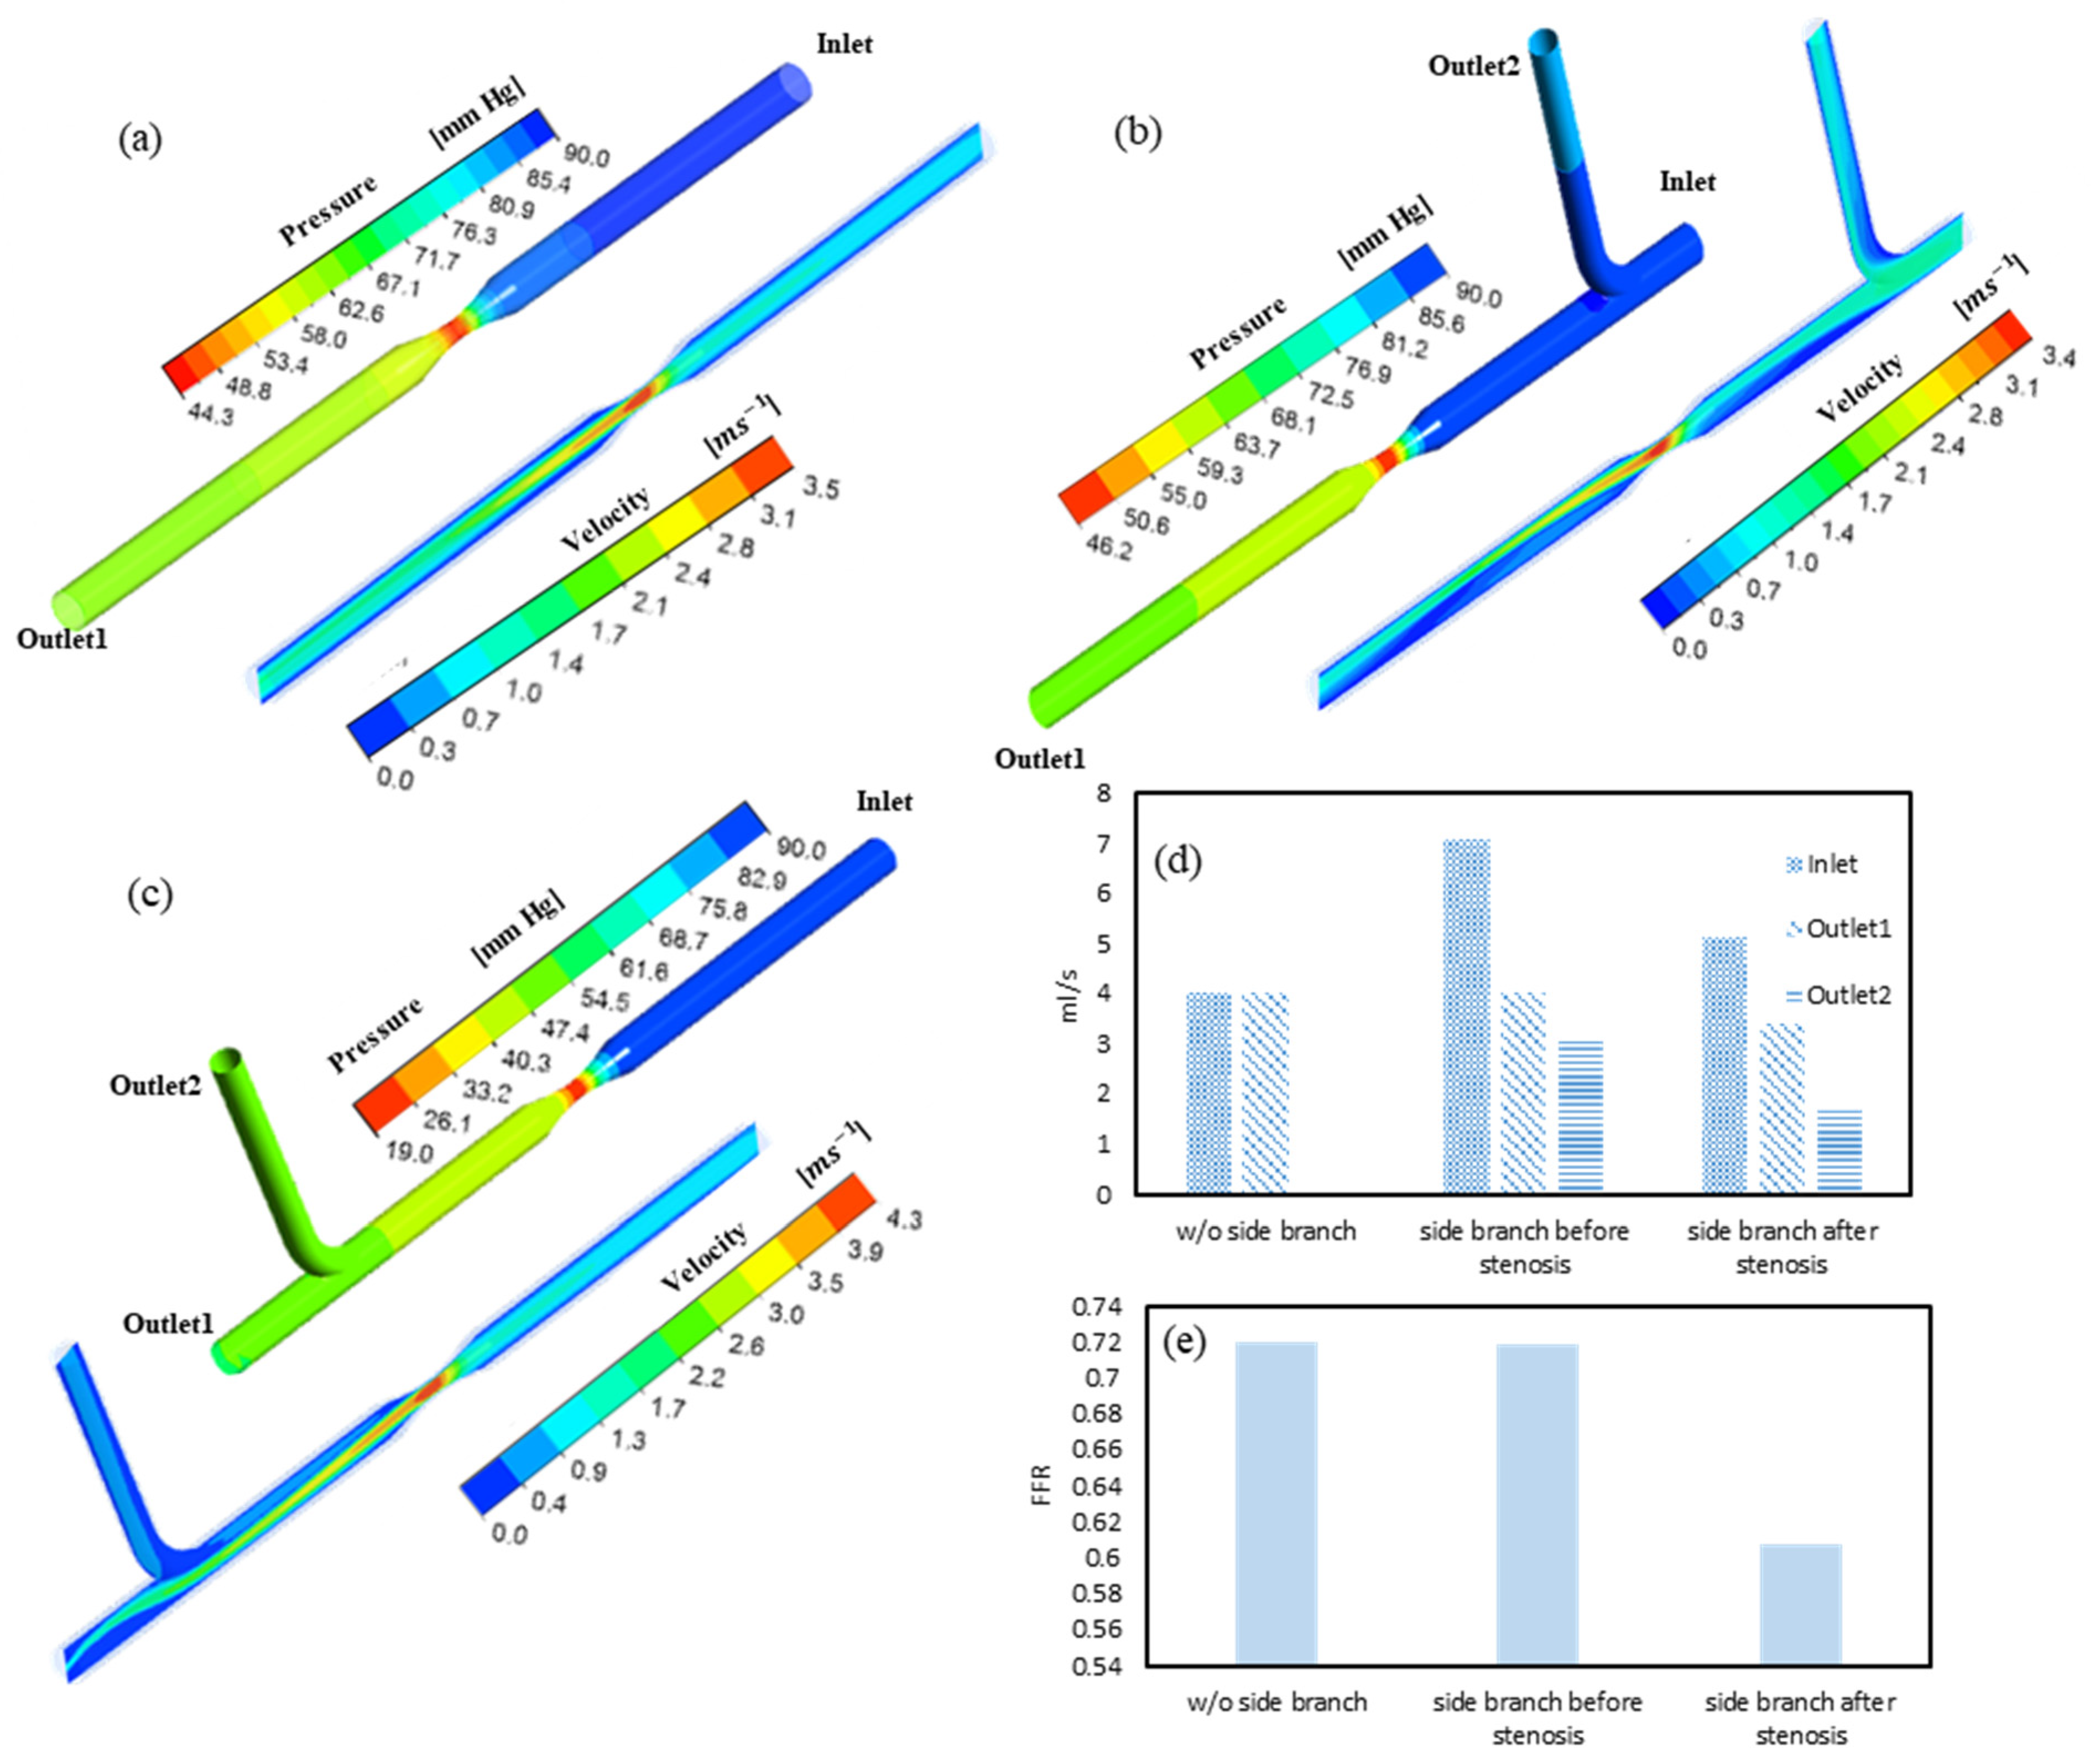

3.1. FFR and Flow Distribution in Idealized Artery Models

3.2. FFR Analysis in OCT-Reconstructed Vessel Models

3.3. Implications on FFR Computation Using OCT Imaging